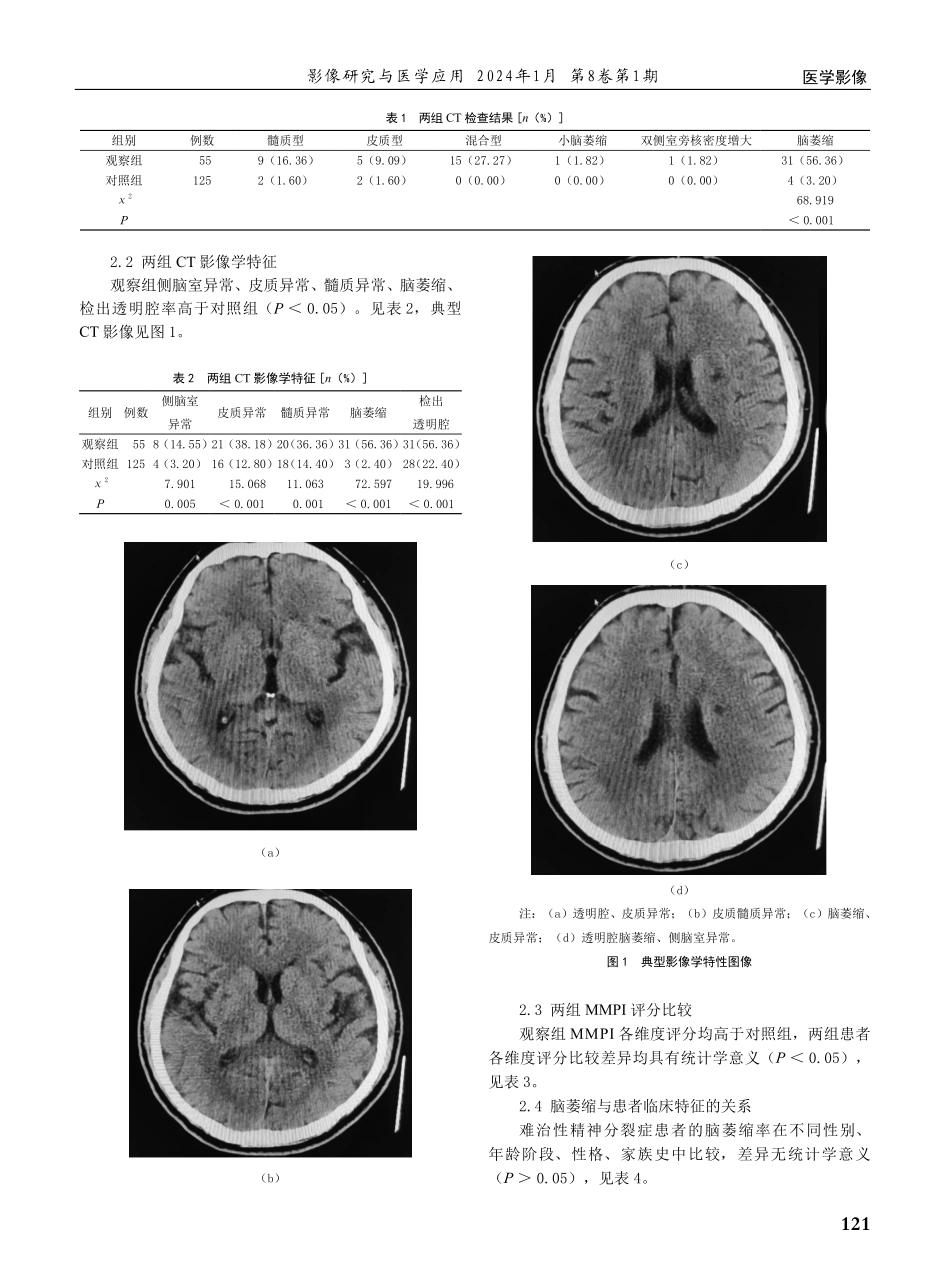

120医学影像影像研究与医学应用2024年1月第8卷第1期颅脑CT在难治性精神分裂症患者中的应用价值及影像学特征分析姚娜(淄博市精神卫生中心<淄博市第五人民医院>影像科山东淄博255000)【摘要】目的:探讨颅脑CT在难治性精神分裂症患者中的应用价值及影像学特征。方法:选取2020年10月—2023年9月淄博市精神卫生中心收治的180例精神分裂症患者,按照病情程度将患者分为难治性精神分裂症患者(观察组,n=55)和普通精神分裂症患者(对照组,n=125)。所有受检者均接受颅脑CT检查,分析两组CT检查结果、影像学特征。结果:观察组脑萎缩检出率为56.36%高于对照组的3.20%(P<0.05)。观察组侧脑室异常、皮质异常、髓质异常、脑萎缩、检出透明腔率分别为14.55%、38.18%、36.36%、56.36%、56.36%,高于对照组的3.20%、12.80%、14.40%、2.40%、22.40%(P<0.05)。观察组MMPI各维度评分均高于对照组(P<0.05)。难治性精神分裂症患者的脑萎缩率在不同性别、年龄阶段、性格、家族史中比较,差异无统计学意义(P>0.05)。结论:难治性精神分裂症颅脑CT检查发现,多数患者伴有脑萎缩及透明隔腔,可根据该特征判断患者的病情,指导临床治疗的开展。【关键词】颅脑CT;难治性精神分裂症;影像学特征【中图分类号】R445.3【文献标识码】A【文章编号】2096-3807(2024)01-0120-04精神分裂症是常见的精神障碍性疾病,该病的病因尚未完全明确,多见于青壮年人群[1]。随着生活压力的增加及生活节奏的加快,精神分裂症的发病人数不断增多。感觉、知觉、情感及行为异常等为精神分裂症的主要特征,患者意识多较正常,部分患者可在疾病进展期间出现认知功能损伤[2]。精神分裂症病程迁延,病情易反复,部分患者经药物及心理治疗后可显著改善症状,另有部分患者长期接受药物治疗的效果不佳,该类患者称为难治性精神分裂症[3]。难治性精神分裂症患者的发病原因虽尚未阐明,但有报道指出脑部器质性病变与其发病存在联系,因此采取有效的措施明确脑部器质性改变意义重大[4]。颅脑CT检查具有简便、无创的优势,可观察颅脑的结构变化情况,此前已被广泛用于精神分裂症的检查,然而关于其在难治性精神分裂症中的应用尚缺乏相关经验[5-6]。本文选取180例精神分裂症患者进行研究,报道如下。1资料与方法1.1一般资料选取2020年10月—2023年9月淄博市精神卫生中心收治的180例精神分裂症患者。按照难治性精神分裂症诊断标准[7]将患者分为难治性精神分裂症患者(观察组,n=55)和普通...